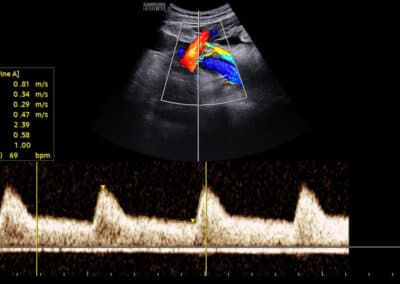

Dopplerovské vyšetření uterinních arterií v 11.-14. týdnu těhotenství

Měření PI (index pulsatility) v uterinních arteriích dle FMF protokolu

Podmínky FMF certifikace pro správné měření PI (index pulsatility) v uterinních arteriích:

FMF certifikát na vyšetření NT (včetně absolvování on-line kurzu o vyšetření v 11.-14. týdnu těhotenství před získáním tohoto certifikátu) Úspěšné složení krátkého on-line testu týkajícího se hodnocení snímků zobrazujících vyšetření ductus venosus Zaslání tří snímků ze správného vyšetření uterinních arterií

Protokol pro správné měření PI (index pulsatility) v uterinních arteriích:

CRL 45-84 mm (11-13+6 týden) Sagitální řez dělohou se zobrazením kanálu děložního hrdla a jeho vnitřní branky, následně mírné sklopení sondy a aplikace Dopplerovského barevného mapování za účelem identifikace uterinních arterií Měření PI (index pulsatility) v oblasti vnitřní branky Gate 2mm Odklon průběhu uterinních arterií 0-30º od vertikální osy Měření PI (index pulsatility) ze třech bezprostředně následujících podobných pulsních vln Kalkulace průměrného PI (index pulsatility) obou uterinních arterií

Ukázka správného snímku zobrazujícího Dopplerovské vyšetření uterinních arterií.